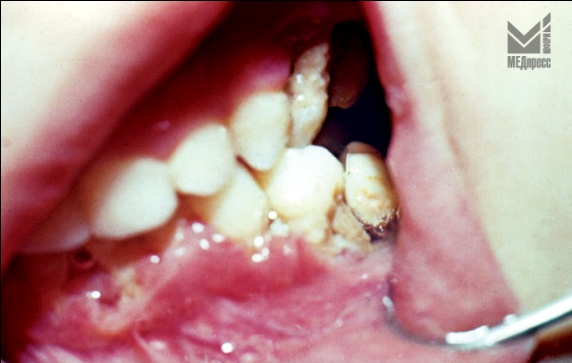

| Рис. 1. Язвенно- некротический гингивит в области 65 и 75 зубов. |